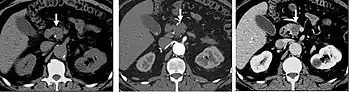

A CT scan image showing a ruptured abdominal aortic aneurysm.